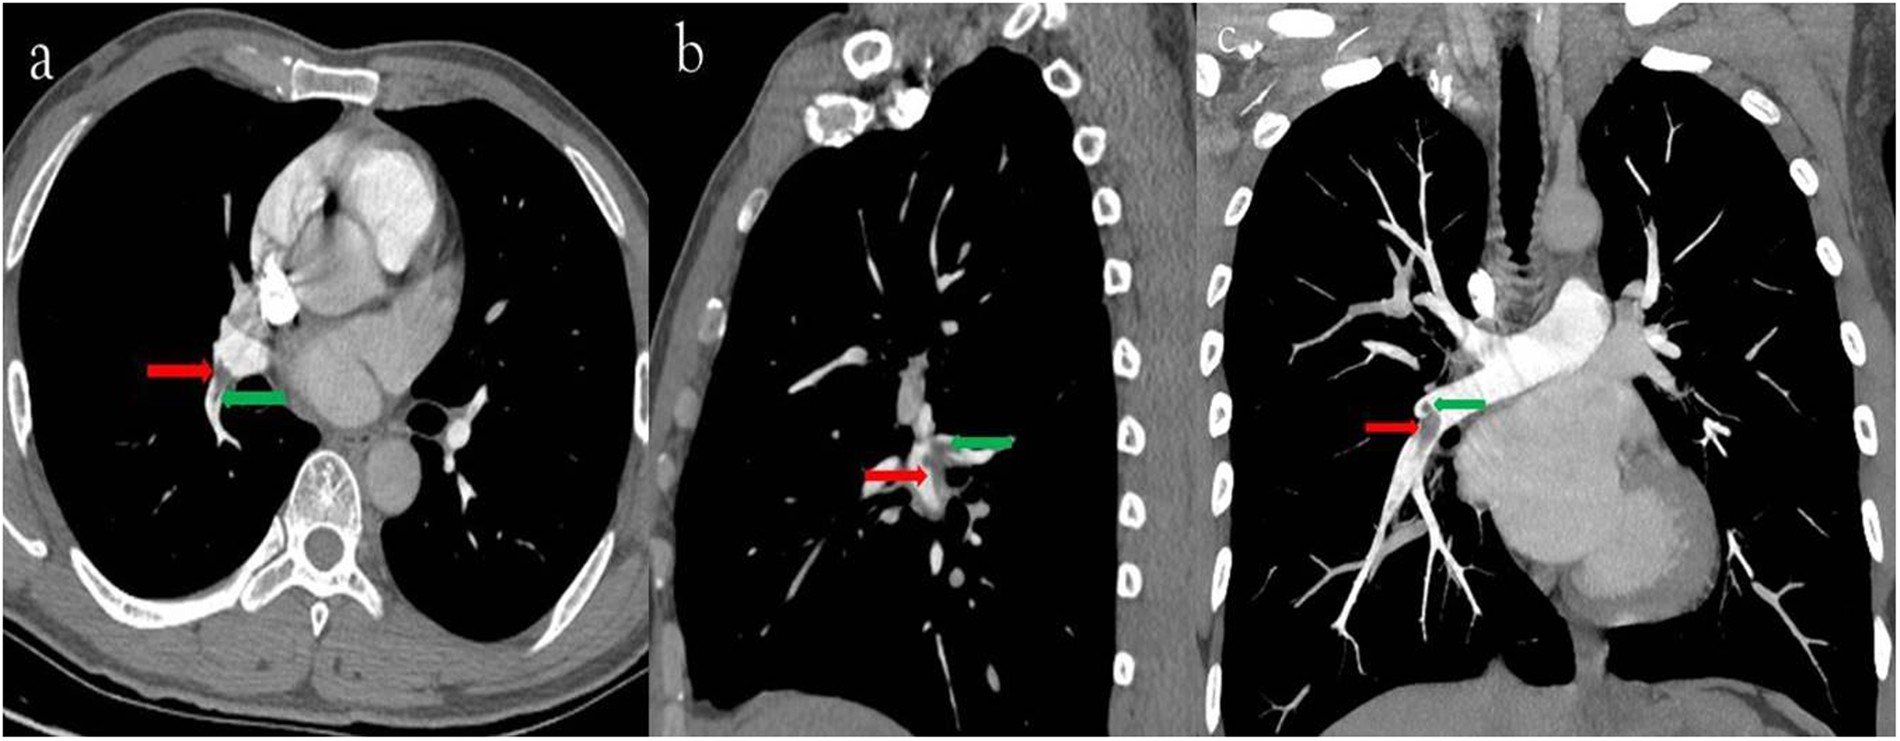

Figure 4

(a) 40-year-old man with pulmonary embolism. The CTPA performed with 120 kVp/40 ml 350 mg I/ml. Filling defects were seen in the right inferior lobe artery (c, axial thin slice image; d, sagital thin slice image; e, coronal MIP image; red arrow) and in the dorsal segmental artery (c, d and e, green arrow).